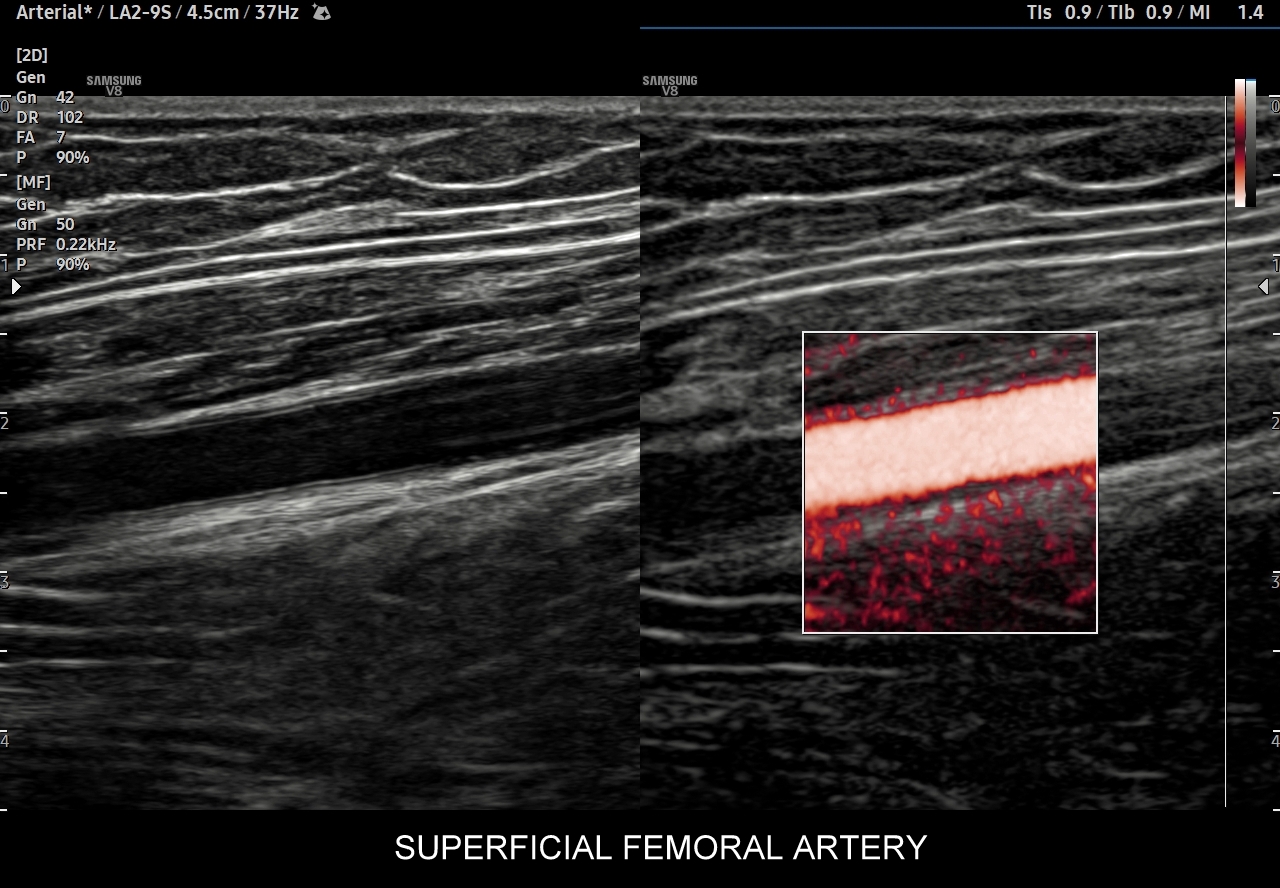

41. Patologie tętnic kończyn dolnych, w tym miażdżyca zarostowa, niedrożności, krążenie oboczne, tętniaki, urazy i rozwarstwienia.

- Badanie USG Doppler tętnic kończyn dolnych.